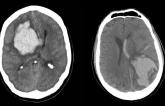

Experts Debate: Is It ‘Nuts’ to Restart Anticoagulation After Lobar ICH?